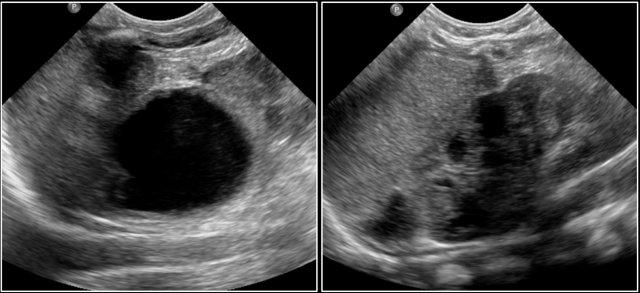

Bé trai 9 tuổi với triệu chứng đau bụng.

Siêu âm và CT cho thấy một cấu trúc dạng nang kèm viêm xung quanh nằm phía trên bàng quang. Siêu âm ghi nhận thành nang có cấu trúc nhiều lớp.

Chẩn đoán trước phẫu thuật là túi thừa Meckel hoặc nang đôi ruột.

Trong phẫu thuật, túi thừa Meckel đã được cắt bỏ.